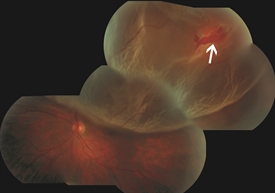

Superior macula-involving retinal detachment with a retinal tear identified with arrow |

Same patient one day after treatment. The retina is reattached and a gas bubble is visible at the top of the eye. |